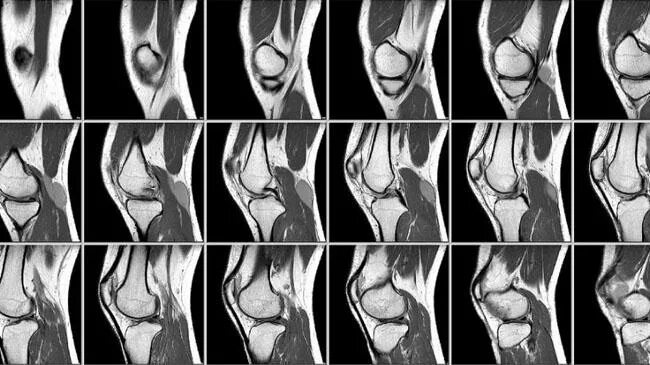

Мрт колена время